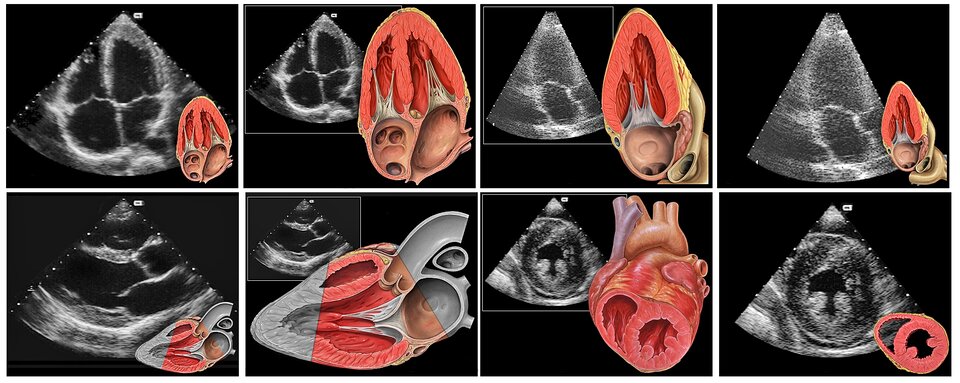

- echokardiografia (USG serca) - służy do oceny pracy i budowy serca, pozwala wykryć wady w budowie serca i jego choroby,